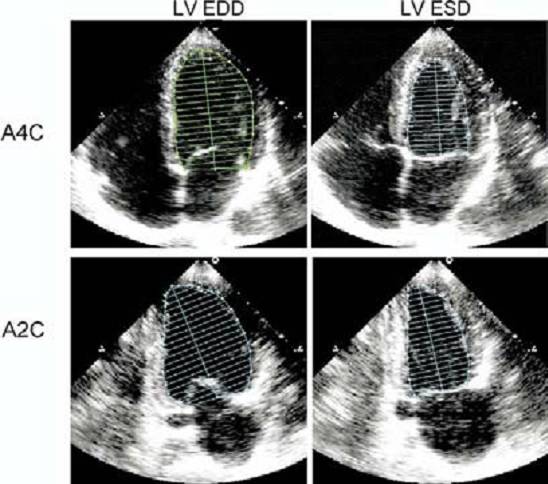

第二个是Simpons法 :目前用的比较多,它的原理是:一较大几何体的体积可视为由若干个具有相似形状的较小几何体的体积所组成。

这一方法亦称为圆盘相加法。优点是,几何形态的假设较少,准确性较高。对有左室形变的心脏也能进行心功能评估。但是Simpons法也未能成为完美,因为它要求良好显示左室四腔心切面和两腔心切面,对超声操作者要求较高。而且测量的两个切面也不在同一个心动周期内,不够严谨。如遇到心内膜边界显示不清时,会影响结果。